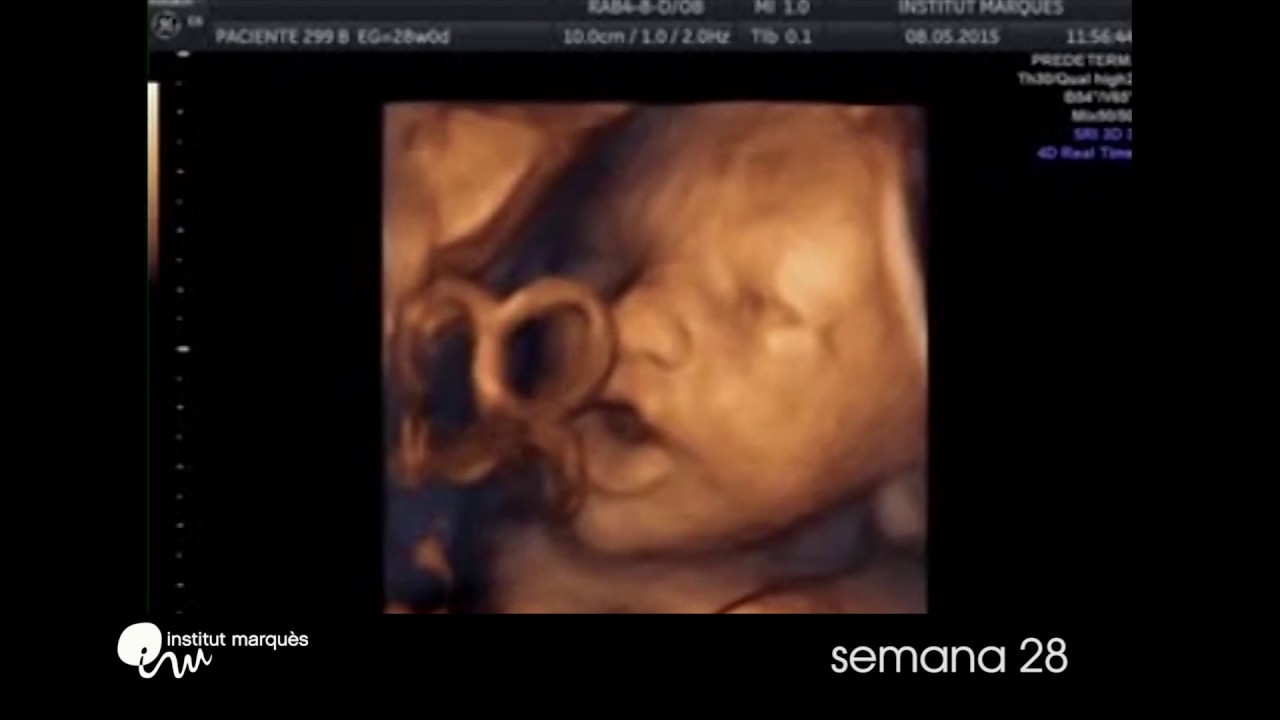

Barcellona Feto Reagisce Alla Musica Gia Alla 16esima Settimana Di Gestazione

Il Feto Canta Bach A 16 Settimane La Scienza Esulta La Rete Impazzisce Magazine Delle Donne

La Ricerca Gia A 16 Settimane Il Feto Canta E Balla Se Sente Musica Video Il Mattino It

Bambino Sente Musica Nella Pancia Pianetamamma It